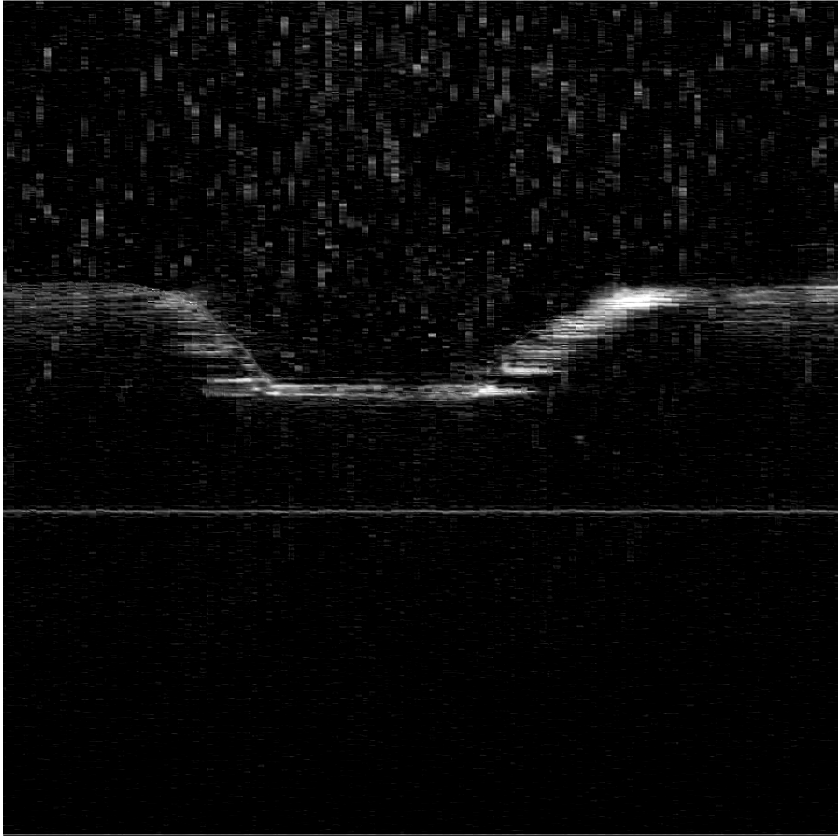

We consider an OCT B-scan image of a bone piece, shown on the left of Fig. 8. This image is produced by measuring across the cut (yielding the cut profile) while ablating the bone using a laser beam coming from top. In the center and right of Fig. 8, we see the eigenfunctions and , respectively. It is easy to see that is extremely relevant to the reconstruction of and the eigenfunction holding information only on the noise.

Now, we segment the noise out, produced by water droplets of the cooling spray, from the image using (16). The filtered image is shown on the right of Fig. 8.